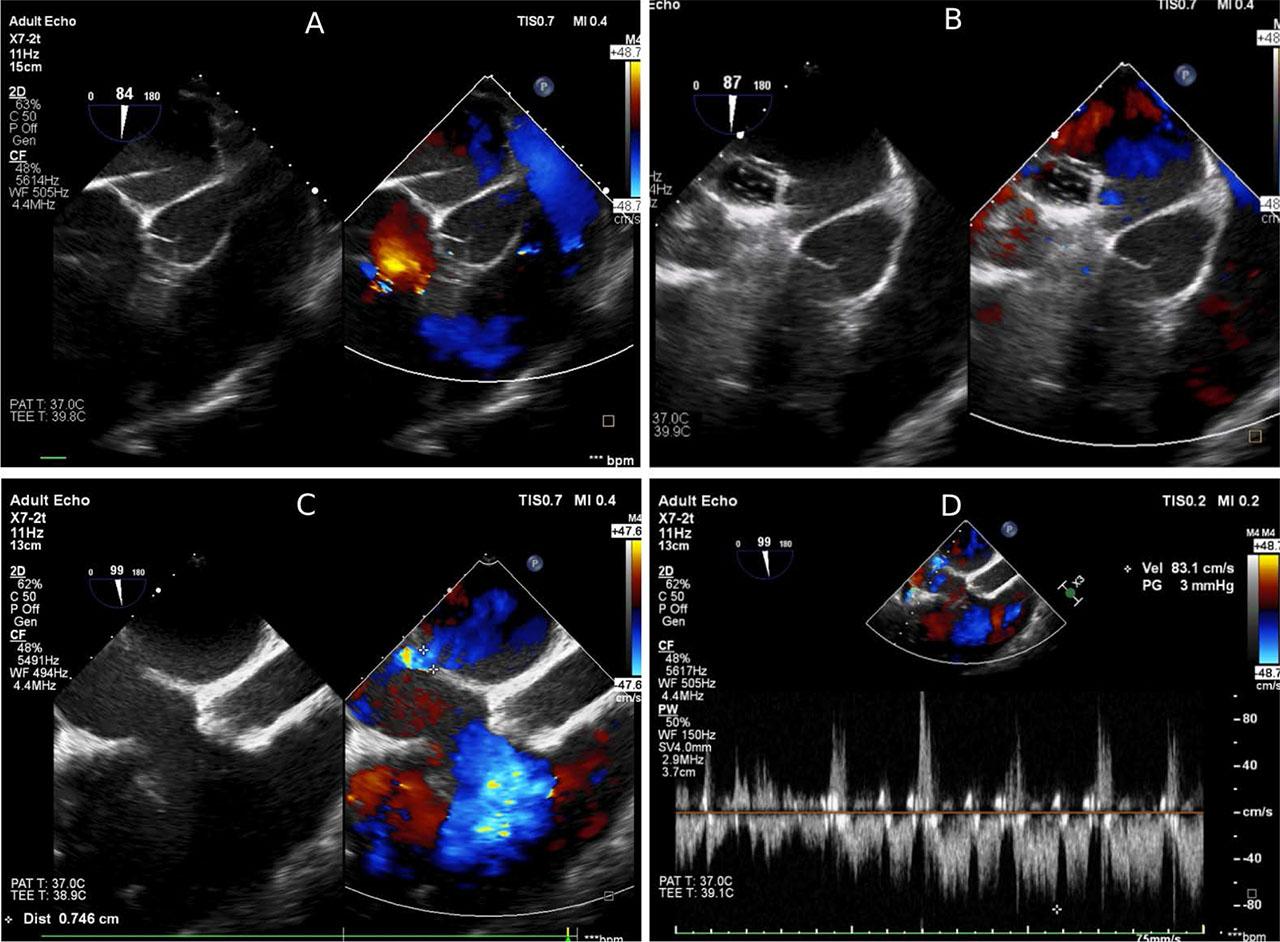

To decompress the left heart, the next day an echocardiography-guided transseptal puncture was performed through the interatrial septum, followed by balloon dilation of the interatrial communication, which did not manage to decrease the congestion of the left heart (Figure 2). After two more days of critical state of the patient, central cannulation was done (right atrium – ascending aorta) with another cannula for left atrial venting, and the patient remained with an open sternum. This led to a good decompression of the left heart. The patient was in a desperate situation, needing a heart transplant while being on VA-ECMO. After three more days, he underwent an orthotopic heart transplantation by bicaval technique.

Echocardiography-guided transseptal puncture through the interatrial septum. A. Transseptal needle. B. Balloon dilation of the interatrial communication. C. Doppler color-flow in atrial septal defect. D. Pulsed-wave Doppler revealing unrestrictive atrial septal defect.